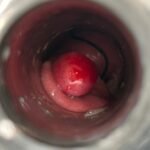

LASER LIAS FOR ANAL FISSURES AND BANDING OF HEMORRHOIDS